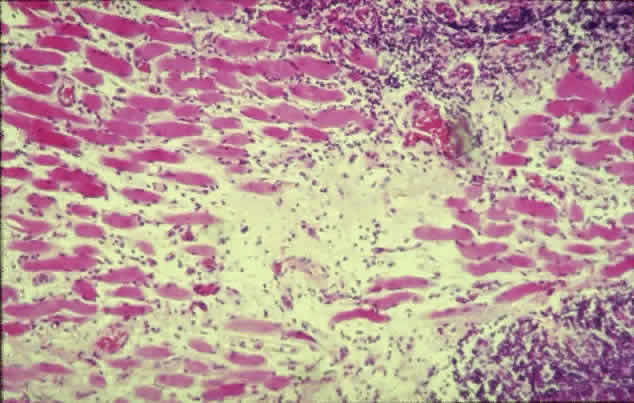

The inflammatory infiltration of the extraocular muscles consists principally of activated T-cells together with smaller numbers of B-cells, macrophages, and mast cells.16 The infiltration is mainly interstitial and is accompanied by increased fibroblastic activity induced by cytokines derived from the immune cells, leading to deposition of glycosaminoglycans and collagen as well as edema. The eventual outcome is fat cell infiltration and fibrosis (Fig. 3). The muscle fibers appear normal, with the exception of subsarcolemmal deposits of lipid and glycogen, and there is an absence of muscle-cell destruction.

Fig. 3. Histologic section of an extraocular muscle in thyroid-associated ophthalmopathy. There is diffuse lymphocytic infiltration accompanied by fibrotic elements (light pink) affecting muscle fibers (dark pink). (Courtesy of Mr. Peter Fells, Moorfields Eye Hospital, London.)